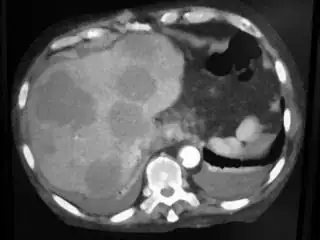

Below I apply two successive morphological openings to the image using a 3x3 circular kernel, and then apply k-means clustering to the gray levels. From your sample images and some I found on the internet, I decided to set k = 4. If you are using high-resolution images, first downsample them to dimensions ~400-600. Otherwise the morphological operation may not have a significant effect, and the k-means will be slow.

Below are some of the opened and segmented images. Of course there's more to be done in terms of

- separating out the liver region

- generalizing this to a large dataset

but hope this is at least a starting point.